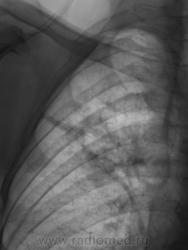

И откуда он берется? Очередной контроль после флюорографии.

Контроль передвижного флюорографа.

Сегодня дообследовали.

да тубркулеза у Вас хватает!

Не оказался "пневмонией". Сегодня пришел коллега фтизиатр записать изображения на диск, посылает пациента в ОПТД, палки найдены.